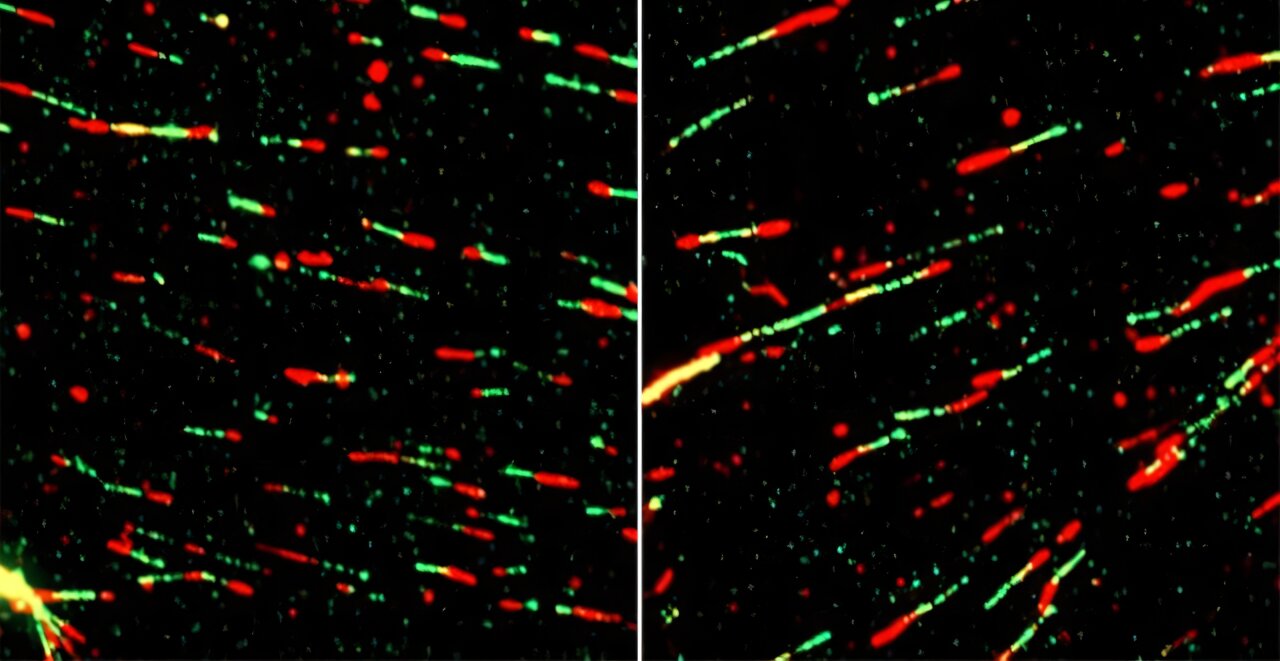

More than 400 million people experience a urinary tract infection every year, and some epidemiological studies…